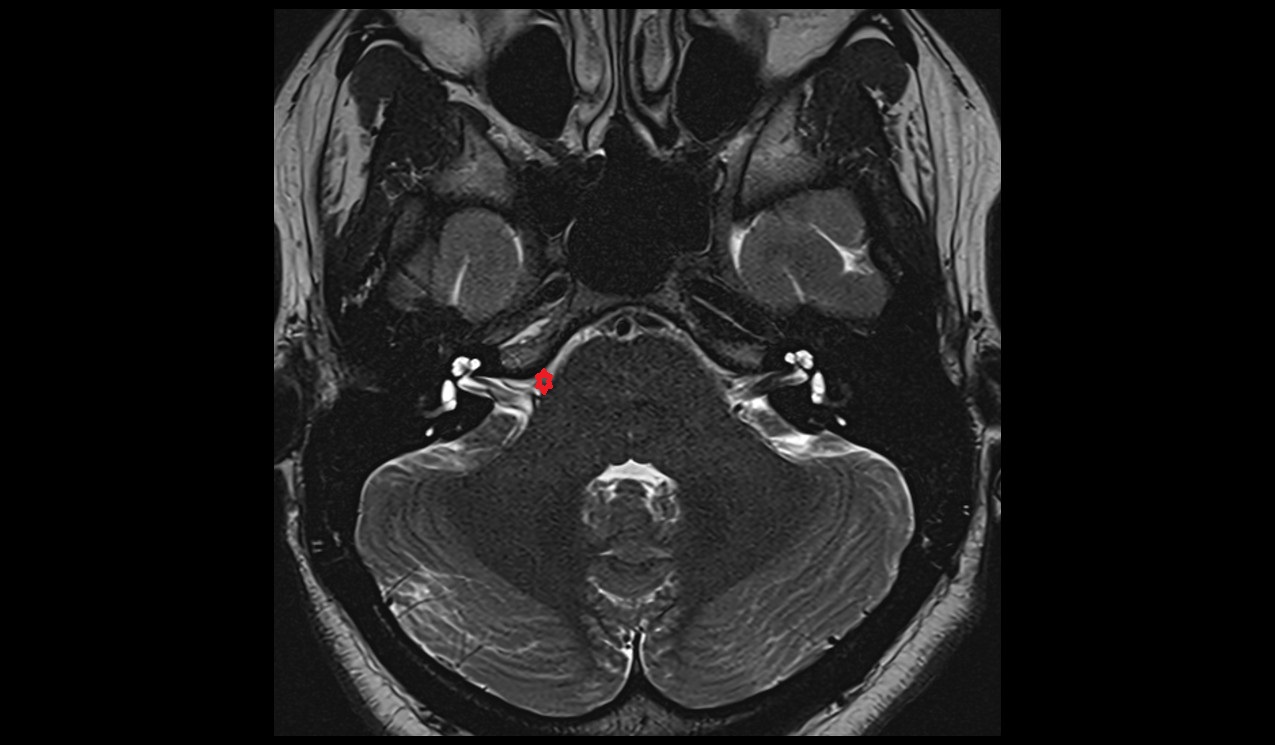

- Lateral aperture of fourth ventricle (foramen of Luschka)